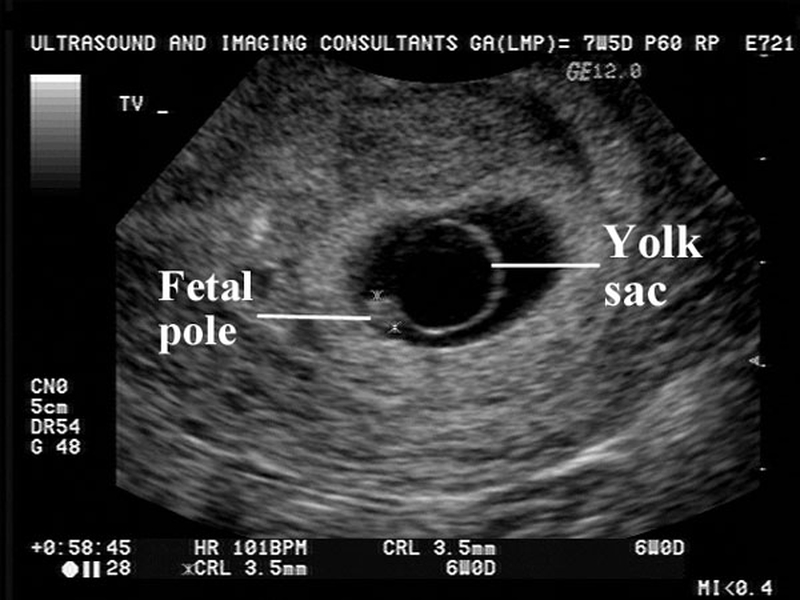

Trong thời kỳ mang thai thì tim thai sẽ hình thành và bắt đầu đập kể từ ngày thứ 22 sau khi thụ thai. Thông thường tim thai sẽ xuất hiện vào tuần thứ 6 đến 7 của thai kỳ thông qua các kỹ thuật siêu âm hiện đại, giúp mẹ có thể dễ dàng nhận biết và nghe được tim thai.

Nhưng có nhiều trường hợp do chu kỳ kinh nguyệt cũng như do sự phát triển của phôi thai mà phải đến tuần thứ 8 - 10 thì mẹ bầu mới có thể nghe được nhịp đập của tim thai. Trong giai đoạn đầu khi mới hình thành thì tim thai phát triển ở hình dạng ống khá đơn giản sau đó xoắn, phân chia, cuối cùng sẽ hình thành trái tim với bốn buồng và van tim. Ở những tuần tiếp theo tim thai sẽ phát triển và nhịp cũng rõ hơn, mẹ bầu có thể dễ dàng cảm nhận được nhịp tim của con mình.

Khoảng thời gian thích hợp để siêu âm tim thai là tuần thứ 6 - 9 của thai kỳ, giai đoạn này sẽ giúp mẹ bầu xác định chính xác mình có mang thai hay không, nhận biết được tuổi thai và đồng thời kiểm tra tim thai có đang hoạt động hay không. Bên cạnh đó thông qua việc siêu âm tim thai sẽ có thể sàng lọc được tình trạng khuyết tật tim bẩm sinh, tim một thất, teo van động mạch phổi,.... Chính vì vậy mà không nên bỏ qua siêu âm tim thai ở giai đoạn này, bởi nếu không thăm khám, không biết được sự phát triển, tồn tại của bé sẽ rất dễ gặp phải những vấn đề không mong muốn.